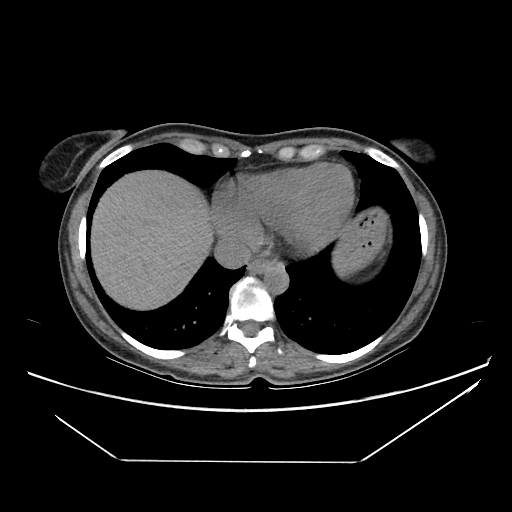

Image Grid

4Γ—3 grid: Rows show different image types (Original NATIVE, Reconstructed NATIVE, Original VENOUS, Generated VENOUS), Columns show windowing techniques (No Window, Lung Window, Mediastinum Window)

Original NATIVE CT scan (input)

Full window (WL 1023.5, WW 4095 β†’ Low βˆ’1024, High +3071)

Actual HU range: [-160.0, 240.0]

Lung window (WL -600, WW 1500 β†’ Low βˆ’1350, High +150)

Actual HU range: [-160.0, 150.0]

Mediastinum window (WL 40, WW 400 β†’ Low βˆ’160, High +240)